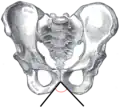

Angle sous-pubien féminin